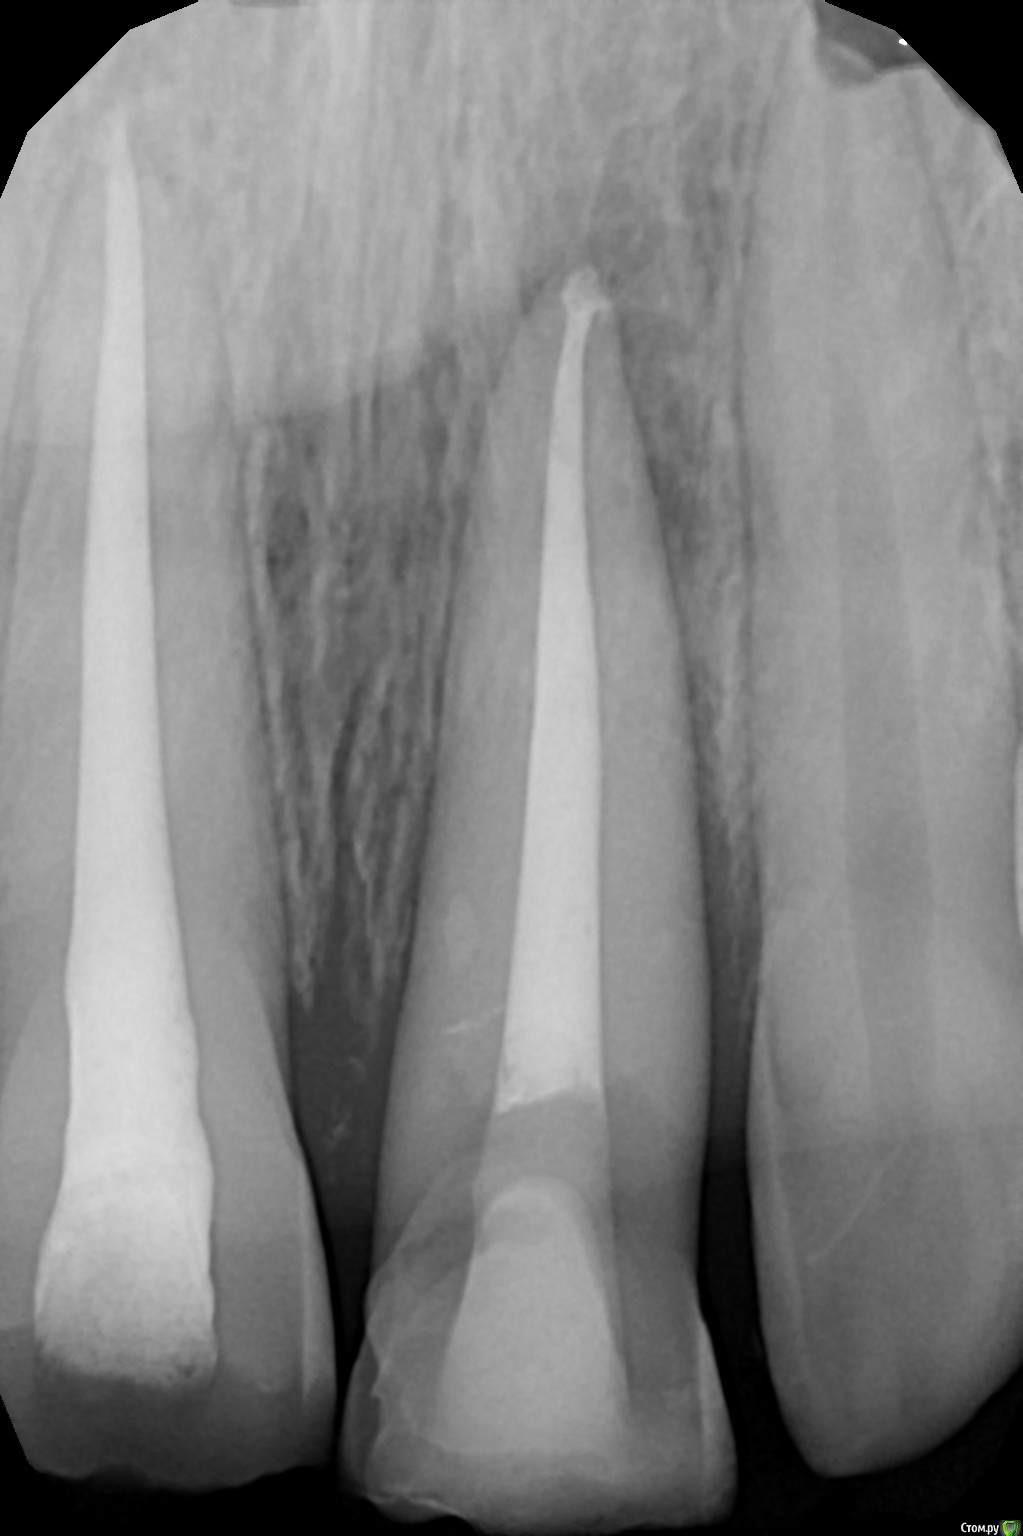

Art 7 Опубликовано 11 августа, 2017 Поделиться Опубликовано 11 августа, 2017 ставишь стекловолоконную балку между апроксимальных поверхностях соседних зубов) Ссылка на комментарий

kamranchick Опубликовано 11 августа, 2017 Автор Поделиться Опубликовано 11 августа, 2017 ставишь стекловолоконную балку между апроксимальных поверхностях соседних зубов)Спасибо Артурчик)Попробуем так))) просто шатается сильно, страшно трогать пока что) Ссылка на комментарий

kamranchick Опубликовано 11 августа, 2017 Автор Поделиться Опубликовано 11 августа, 2017 Это обычная силиконовая каппа ?вытягиваем, потом стабилизация ? Как на долго?капу сделали вакуум формером, помоему она пластмассовая вроде. стабилизация 2-3 месяца... Ссылка на комментарий